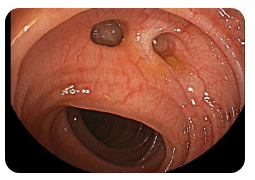

🍽️ 왼쪽 옆구리 통증 소화불량

소화불량은 위장 기능 저하로 인해 복부 불쾌감과 함께 옆구리 통증을 유발할 수 있습니다. 특히 식사 후 통증이 나타난다면 위염이나 위궤양, 장운동 이상을 의심할 수 있습니다. 복부 팽만, 잦은 트림, 속쓰림 등의 증상이 함께 나타날 수 있으며, 불규칙한 식습관과 스트레스가 원인이 될 수 있습니다. 증상이 지속된다면 내시경 검사를 통해 위장 질환을 확인하는 것이 필요합니다.